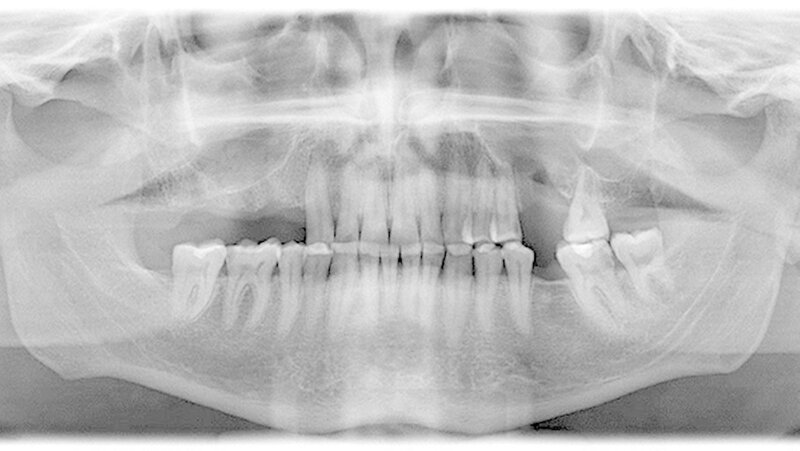

Das angefertigte Orthopantomogramm (OPT) stellte den aktuellen Zahnstatus mit dem Nebenbefund einer röntgendichten Verschattung im Sinne eines Fremdkörpers unterhalb des rechten Kieferhöhlendachs dar (Abbildung 1). Es folgte die Anfertigung eines NNH-CT zur genauen Lokalisierung des Fremdkörpers (Abbildung 2) für die anschließende OP-Planung.

In unserem Fall zeigte sich der röntgenopake Fremdkörper im OPT als Zufallsbefund. Zur genauen Lokalisation ist jedoch eine zwei- bis dreidimensionale radiologische Darstellung notwendig [Ferguson, 2014]. Bei der zweidimensionalen Darstellung bietet sich zum OPT ein Fernröntgenseitenbild und bei der dreidimensionalen ein DVT, NNH-CT sowie im Fall von nicht ferromagnetischen Fremdkörpern auch ein MRT an.